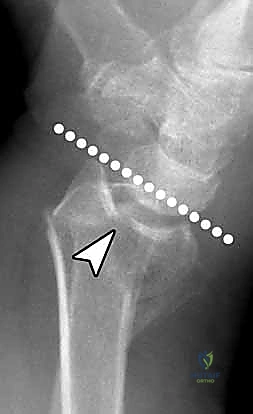

تُعرف كسور الكعبرة البعيدة بأنها تشمل منطقة الكردوس (Metaphysis)، وتحديداً المنطقة الواقعة ضمن طول السطح المفصلي الذي يعادل أوسع جزء من الرسغ بأكمله. في عياداتنا، نقوم بتقييم هذه الكسور بدقة متناهية بناءً على عدة خصائص رئيسية تحدد مسار العلاج:

- الموقع والاتجاه: هل يشمل الجانب الأمامي (الراحي - Volar) أم الخلفي (الظهري - Dorsal)؟

يعتمد الدكتور محمد هطيف على أحدث التقنيات التشخيصية، حيث يبدأ بـ الأشعة السينية (X-rays) في وضعيات متعددة. وفي حالات الكسور المعقدة التي تمتد إلى داخل المفصل، يتم إجراء تصوير مقطعي محوسب (CT Scan) لبناء صورة ثلاثية الأبعاد للكسر، مما يساعد في التخطيط الجراحي الدقيق.